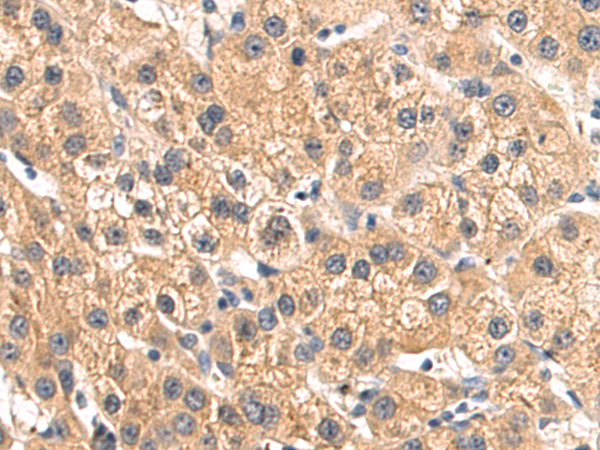

分类: 科研抗体货号: P12199别名: CRT; CT1; CRTR; CTR5; CCDS1应用: IHC反应种属: Human, Mouse, Rat